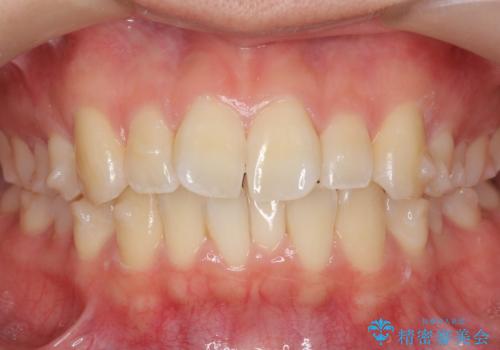

インビザライン モニター治療 前歯のねじれをまっすぐに

- 前歯のねじれを主訴に来院。

インビザラインの部分矯正コースではなく全体矯正コースをご希望でした。

前歯のねじれやがたつきだったため、モニター治療での低価格でのご提案が可能でした。

年齢が10代なこともあり、歯の動きは非常によく、リファインメントなしできれいに並びました。

下の前歯を少し削合して並べています。